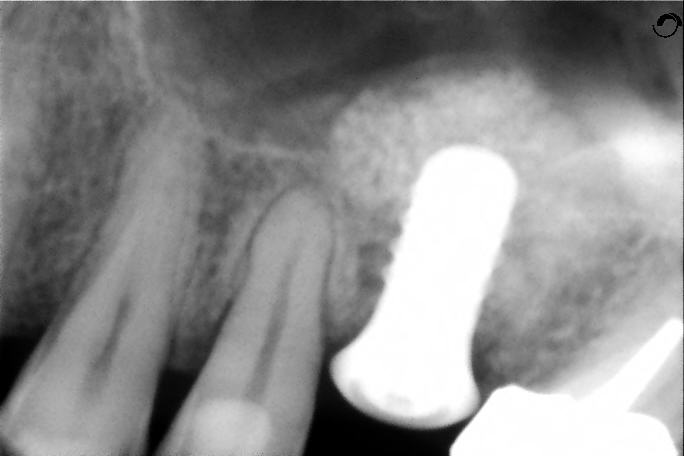

Le sinus lift (accès par voie latérale) : lorsqu’il manque de l’os en arrière du maxillaire supérieur, on accède au sinus par une paroi latérale et on le comble avec nos matériaux. Cela augmente la hauteur osseuse disponible.